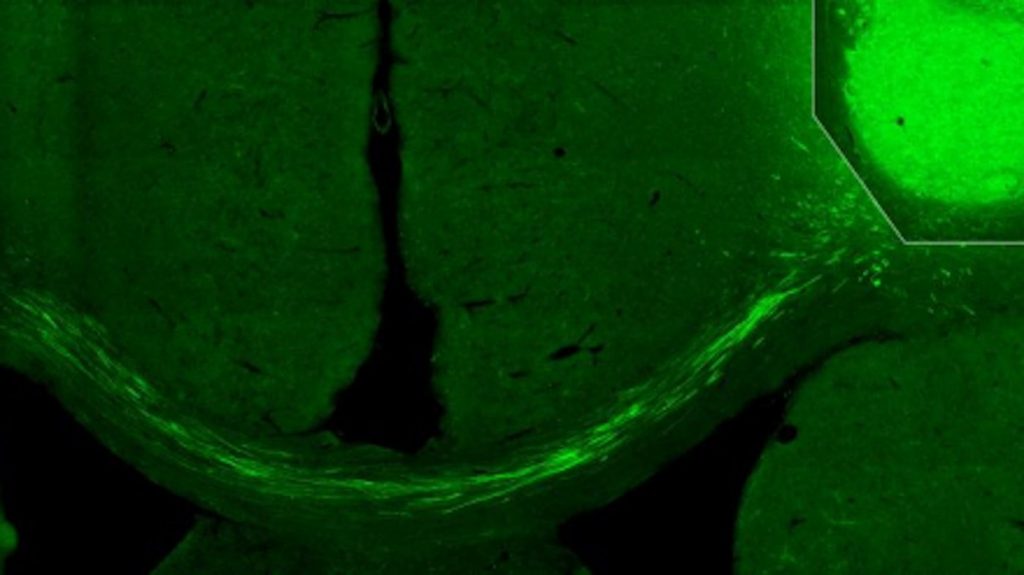

“We have used tracking techniques, electron microscopy and other methods, such as light to switch off activity in the transplanted cells, as a way to show that they really have connected correctly in the damaged nerve circuits. We have been able to see that the fibers from the transplanted cells have grown to the other side of the brain, the side where we did not transplant any cells, and created connections. No previous study has shown this,” says Kokaia, who—even though he and colleague senior professor Olle Lindvall have studied the brain for several decades—was surprised by the results.

The researchers have used human skin cells that have been reprogrammed in the laboratory to become nerve cells. They were then transplanted into the cerebral cortex of rats, in the part of the brain that is most often damaged after a stroke. Now the researchers will undertake further studies.

Photo by Lund University.